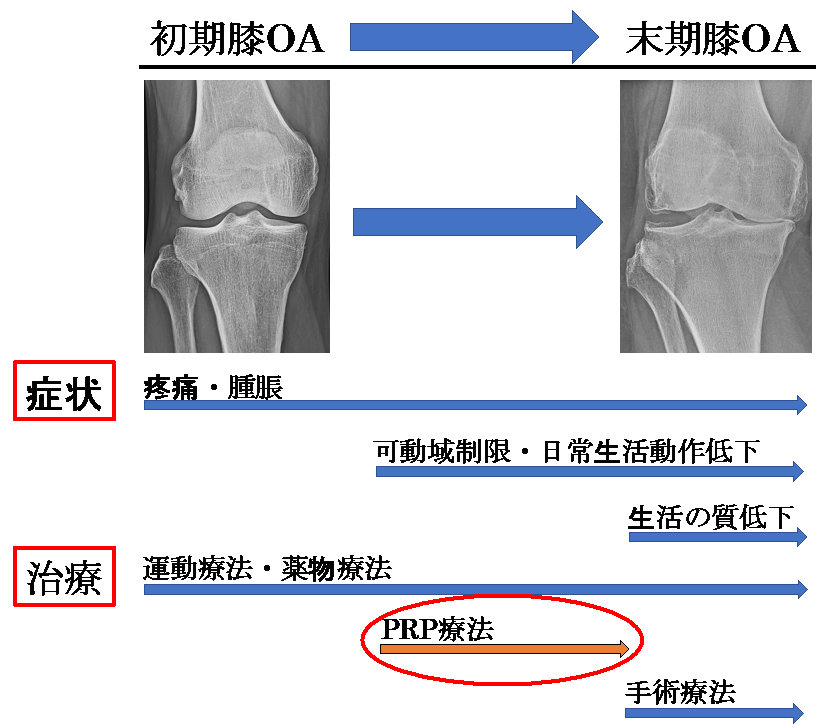

変形性膝関節症は、加齢などにより関節軟骨や半月板が変性・消失する疾患で膝関節痛や可動域制限を生じ、病態が進行すると日常生活動作(ADL)や生活の質(QOL)が低下します。わが国では40歳以上の有病者数は2500万人と推定されており、今後の高齢者人口の増加に伴い有病者数も増加すると考えられています。

変形性膝関節症の治療は初期には減量や運動療法を行いますが、症状の進行に伴い内服薬・外用薬・関節内注射などの薬物療法や手術療法の適応となります。

このような状況を踏まえ、薬物療法と手術療法の間を埋める第3の治療法としてPRP療法が開発されました。本治療法は、従来の保存治療では効果が少ないが現段階ではまだ手術を考えていない患者さんに対して適応があります。